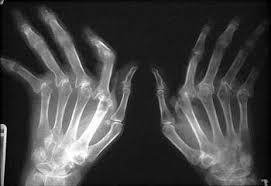

Os sintomas mais comuns são os da artrite (dor, edema, calor e vermelhidão) em qualquer articulação do corpo sobretudo mãos e punhos. O comprometimento da coluna lombar e dorsal é raro mas a coluna cervical é frequentemente envolvida. As articulações inflamadas provocam rigidez matinal, fadiga e com a progressão da doença, há destruição da cartilagem articular e os pacientes podem desenvolver deformidades e incapacidade para realização de suas atividades tanto de vida diária como profissional. As deformidades mais comuns ocorrem em articulações periféricas como os dedos em pescoço de cisne, dedos em botoeira, desvio ulnar e hálux valgo (joanete).

• Alterações radiográficas: erosões articulares ou descalcificações localizadas em radiografias de mãos e punhos.